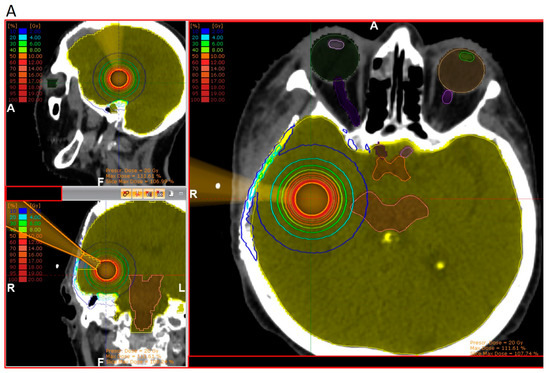

According to pathology-based reports on tissue infiltration surrounding BM, a clinical target between 1 and 4 mm should be considered in the radiotherapy adjuvant setting, depending on the primary histology [33,35]. With approximately 80% of the prescribed surface dose at 3 mm from the surface, kV IORT provides an outstanding treatment outline while avoiding the usually large volumes required during adjuvant SRS. Subsequent dosimetric comparisons between IORT and SRS as dose-escalation strategies for resected glioblastoma and BM, respectively, demonstrated up to three times lower brain V12G (volume of brain receiving 12 Gy) results, favoring IORT [181,182]. An exemplary dosimetric comparison between both modalities is displayed in Figure 2 [181].

Figure 2.

Three-dimensional view of dose distribution profiles, comparing (A) IORT and (B) SRS for the same target. Reprinted with permission from Sarria et al. [181]. Copyright year 2021, copyright owner’s name Sarria et al. Under the terms of the Creative Commons Attribution License (CC BY) [181].